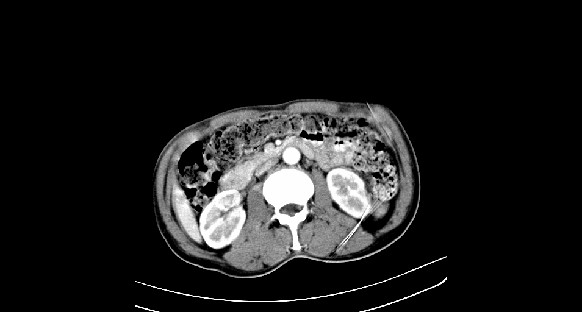

男性,70岁,体检b超发现左肾占位,请各位战友发表一下观点

左肾有两个病灶,且较大的病灶内可见点状钙化灶,增强扫描边缘也是呈渐进性强化,中央部分未见明显强化

考虑左肾脏错构瘤可能,不除外肾癌。

肾癌较肾aml可能大,建议mri,若t2明显高信号者则肾癌基本诊断明确。